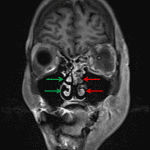

- T2/FLAIR signal hyperintensity in the left sphenoid sinus, left greater than right maxillary sinuses, and throughout bilateral ethmoid air cells

- Left periorbital and postseptal T2/FLAIR signal hyperintensity and enhancement with slight left proptosis

- T2/FLAIR signal hyperintensity and enhancement in the left masticator space involving the left muscles of mastication and extending into the left parapharyngeal space

- Hypoenhancement of the left middle and inferior nasal turbinates

Findings highly concerning for invasive fungal sinusitis with sinus disease involving the left sphenoid sinus, left greater than right maxillary sinuses, and bilateral ethmoid air cells and contiguous extension with left preseptal and postseptal orbital cellulitis, cellulitis/myositis involving the left masticator and parapharyngeal spaces, and evidence of intracranial extension with left superior ophthalmic vein and left cavernous sinus thrombosis. No peripherally enhancing collection to suggest abscess. No convincing enhancement of the left ophthalmic artery is concerning for thrombosis, which could be further evaluated with CTA or catheter angiography. Recommend urgent surgical consultation.

Hypoenhancement of the left middle and inferior nasal turbinates concerning for necrosis.